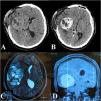

Here, we report the case of a 19-year-old male with a large intracranial SFT, initially treated with transarterial embolization using polyvinyl alcohol (PVA) particles, which failed to achieve proper devascularization of the tumor. Consequently, direct puncture embolization using the SQUID 12 agent was performed. Following successful embolization, complete tumor resection was achieved with significantly reduced intraoperative blood loss and no postoperative neurological deficits.

This case highlights the effectiveness of direct puncture embolization as a viable alternative to traditional transarterial approaches for managing highly vascular intracranial tumors.